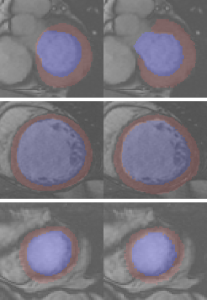

IV-C2 Experiments on Sunnybrook

The slices to be segmented of the 30 cases in Sunnybrook are well located on or below the base of the heart. We segment them with the trained LV-net. In a way similar to the practice in [3], central zones are cropped out as ROIs, which are then used as inputs to LV-net. Comparison of the performance of LV-net and up-to-date state-of-the-art research is presented in Table IV. LV-net is somewhat less accurate on Dice index and on average perpendicular distance (APD). But its robustness makes it comparable or even better than the state-of-the-art on the percentage of good contours (PGC). Examples of predicted masks and ground-truth are shown in Fig.7(b).